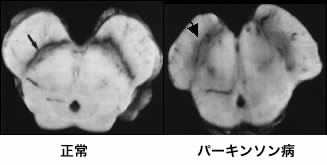

パーキンソン病の原因はドパミンという物質を作り出す中脳(右の写真)の特定の部位の神経細胞が減少するためにおこると言われています。

写真の左側が正常の患者さんで、右側がパーキンソン病の患者さんですが、パーキンソン病の患者さんでは、正常に較べ矢印の部分がぼやけています。これは、その部分の細胞が減っているからです。右の図のようにある程度、中脳のその部分の細胞が減ってしまうと発病すると考えられています。